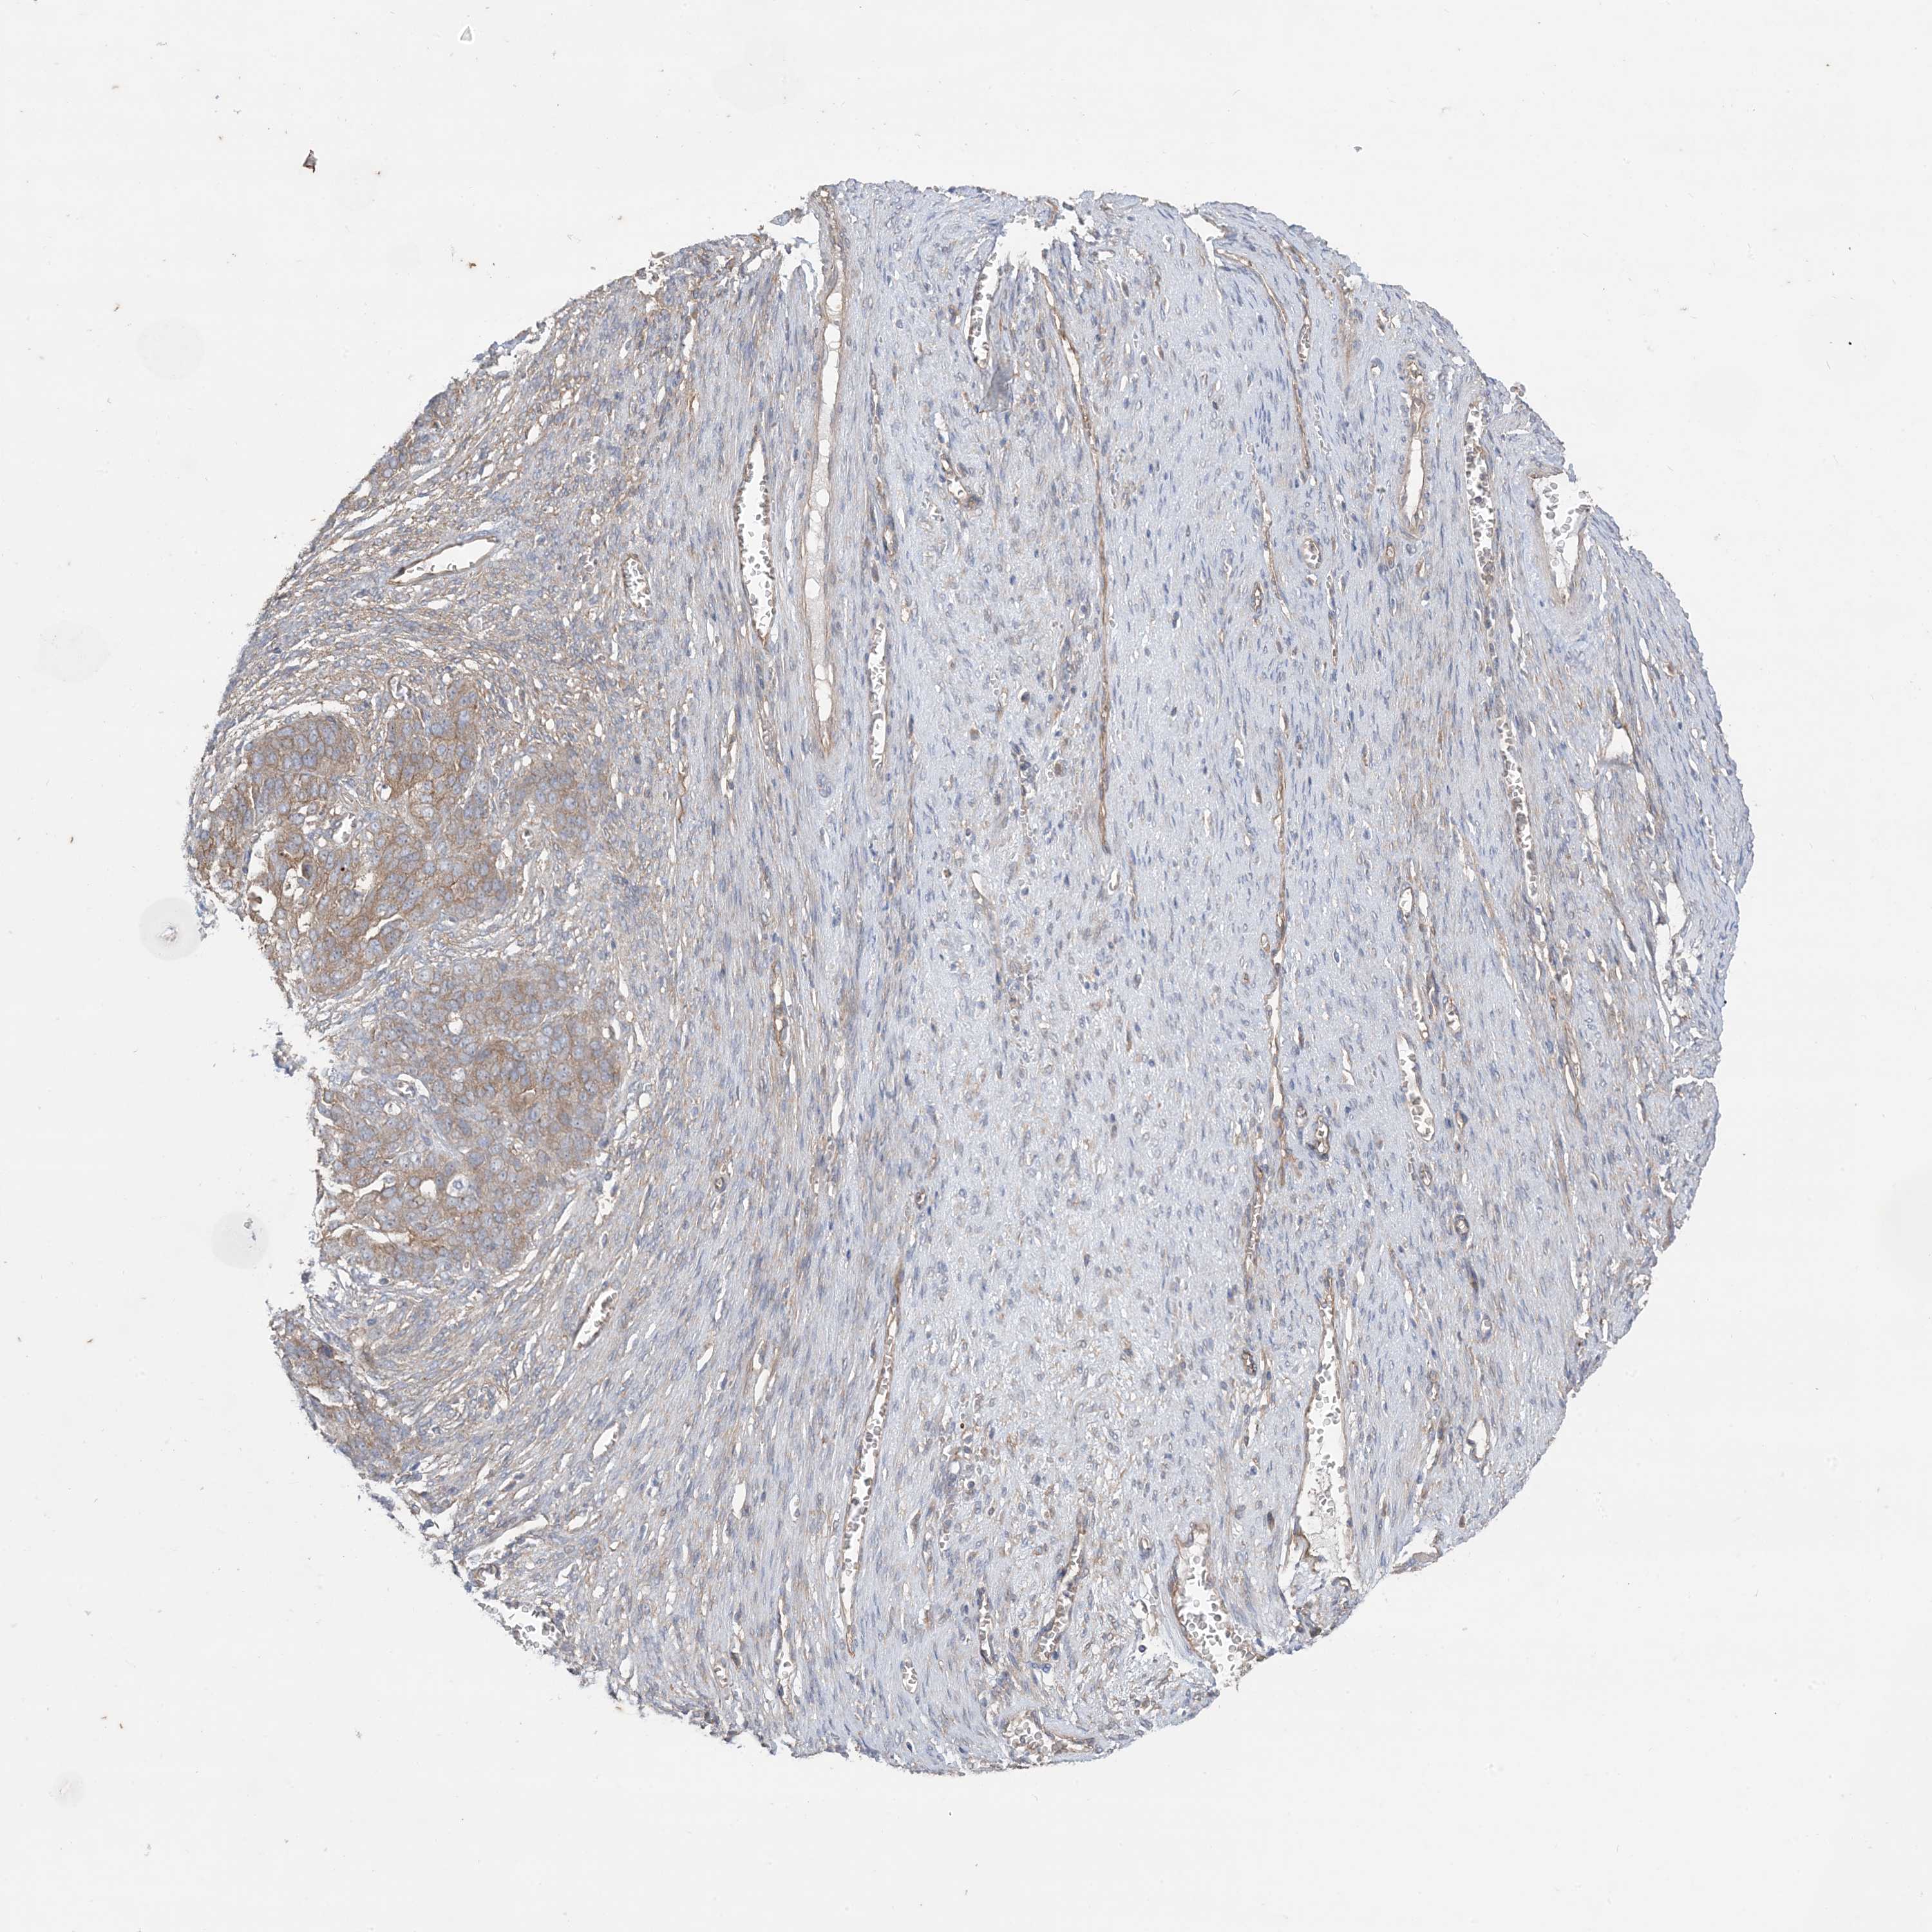

OVARIAN CANCER - Protein expressioni

A mouse-over function shows sample information and annotation data. Click on an image to view it in a full screen mode. Samples can be filtered based on level of antibody staining by selecting one or several of the following categories: high, medium, low and not detected. The assay and annotation is described here.

Note that samples used for immunohistochemistry by the Human Protein Atlas do not correspond to samples in the TCGA dataset.

Antibody stainingi

Antibody staining in the annotated cell types in the current human tissue is reported as not detected, low, medium, or high, based on conventional immunohistochemistry profiling in selected tissues. This score is based on the combination of the staining intensity and fraction of stained cells.

Each image is clickable and will lead to virtual microscopy that enables deeper exploration of all samples and also displays staining intensity scores, fraction scores and subcellular localization as well as patient and tissue information for each sample.

Antibody HPA036290

Staining

High

Medium

Low

Not detected

Intensity

Strong

Moderate

Weak

Negative

Quantity

>75%

75%-25%

<25%

None

Location

Nuclear

Cytoplasmic/membranous

Cytoplasmic/membranous,nuclear

Cystadenocarcinoma, serous, NOS

Carcinoma, endometroid

Cystadenocarcinoma, mucinous, NOS

Carcinoma, NOS